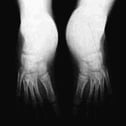

RADIOLOGIA

La radiografía permite apreciar exactamente la cuantía de los desplazamientos óseos. El ángulo astrágalo-calcáneo en la proyección frontal ha desaparecido (ambos huesos están paralelos). En la proyección lateral el astrágalo está horizontalizado. El retropié (calcáneo) en equino, y todo el pie supinado.